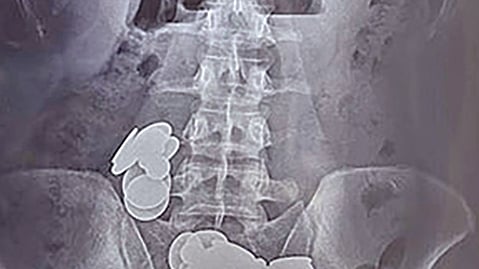

রোগীর স্বজনেরা তাঁর পেটের একটি এক্স–রে করেন। এতে তাঁর পেটে ধাতব মুদ্রা ও চুম্বক খণ্ডের মতো অস্বচ্ছ কিছু বস্তু দেখা যায়। পরে সিটি স্ক্যানে তাঁর পেটে অনেক ধাতব মুদ্রা ও চুম্বকখণ্ড দেখা যায়। এতে তাঁর অন্ত্রের কাজে বাধার সৃষ্টি হয়েছিল। এরপর দ্রুত অস্ত্রোপচারের প্রস্তুতি নেওয়া হয়।

অস্ত্রোপচারের সময় ছোট অন্ত্রের মধ্যে দুটি আলাদা ছিদ্রে ধাতব মুদ্রা ও চুম্বকখণ্ড পাওয়া যায়। চুম্বকের আকর্ষণ দুটি ছিদ্রকে এক জায়গায় টেনে এনেছে। অন্ত্রগুলো খুলে ধাতব মুদ্রা ও চুম্বকখণ্ড বের করা হয়। রোগীর পুরো পেট পরীক্ষা–নিরীক্ষা করে আরও বেশ কিছু ধাতব মুদ্রা ও চুম্বকের খণ্ড পাওয়া যায়।

চিকিৎসকেরা বলছেন, পেট থেকে ১, ২ ও ৫ রুপির মোট ৩৯টি ধাতব মুদ্রা ও হার্ট, গুলি, তারাসহ নানা আকৃতির ৩৭ খণ্ড চুম্বক বের করা হয়েছে।